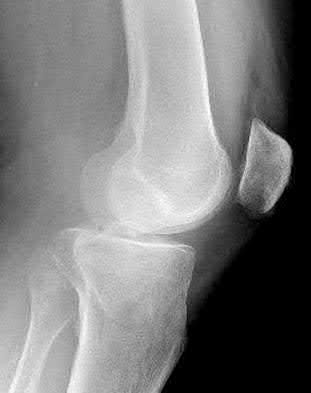

1. # A 32-year-old male sustains the injury shown in Figure A and undergoes treatment as shown in Figure B. Following placement of this implant, what is the best technique to confirm it is not too proud proximally?

1. Lateral radiograph of the knee

2. AP radiograph of the knee

3. Oblique radiographs of the knee

4. Merchant radiograph of the knee

5. Internally rotated 45 degree view of the knee Corrent answer: 1

The safe zone for tibial nail placement as seen on radiographs is just medial to the lateral tibial spine on the anteroposterior radiograph and immediately adjacent and anterior to the articular surface as visualized on the lateral radiograph.

Tornetta et al specifically located the safe zone for nail entry in a study using fresh frozen cadaver knees. The authors found that the safe zone for nail placement is located 9.1+/-5 millimeters lateral to the midline of the plateau and three millimeters lateral to the center of the tibial tubercle. The width of the safe zone averaged 22.9 millimeters and was as narrow as 12.6 millimeters.

The starting point of the of the nail can be best viewed on the lateral knee radiograph, an example of which is shown in Illustration A. Illustration B shows the "sweet spot" for nail insertion as defined by Tornetta.